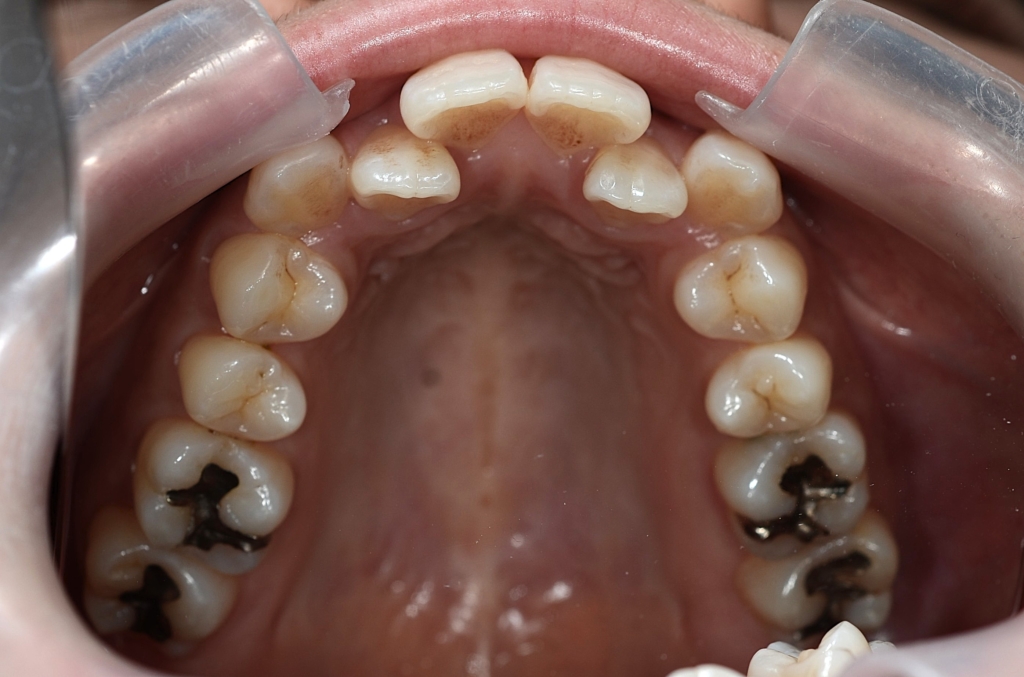

レントゲン写真で確認すると、

この患者さんの場合、

【抜歯】

上下の左右の奥歯を1本ずつ計4本抜歯(4番目の奥歯を抜きました)